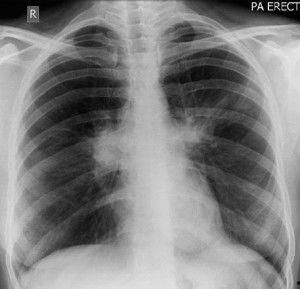

3. 呼吸系统症状:如咳嗽、哮喘、支气管痉挛等。

其中,支气管痉挛是最严重的症状之一,严重时甚至可能导致呼吸困难。